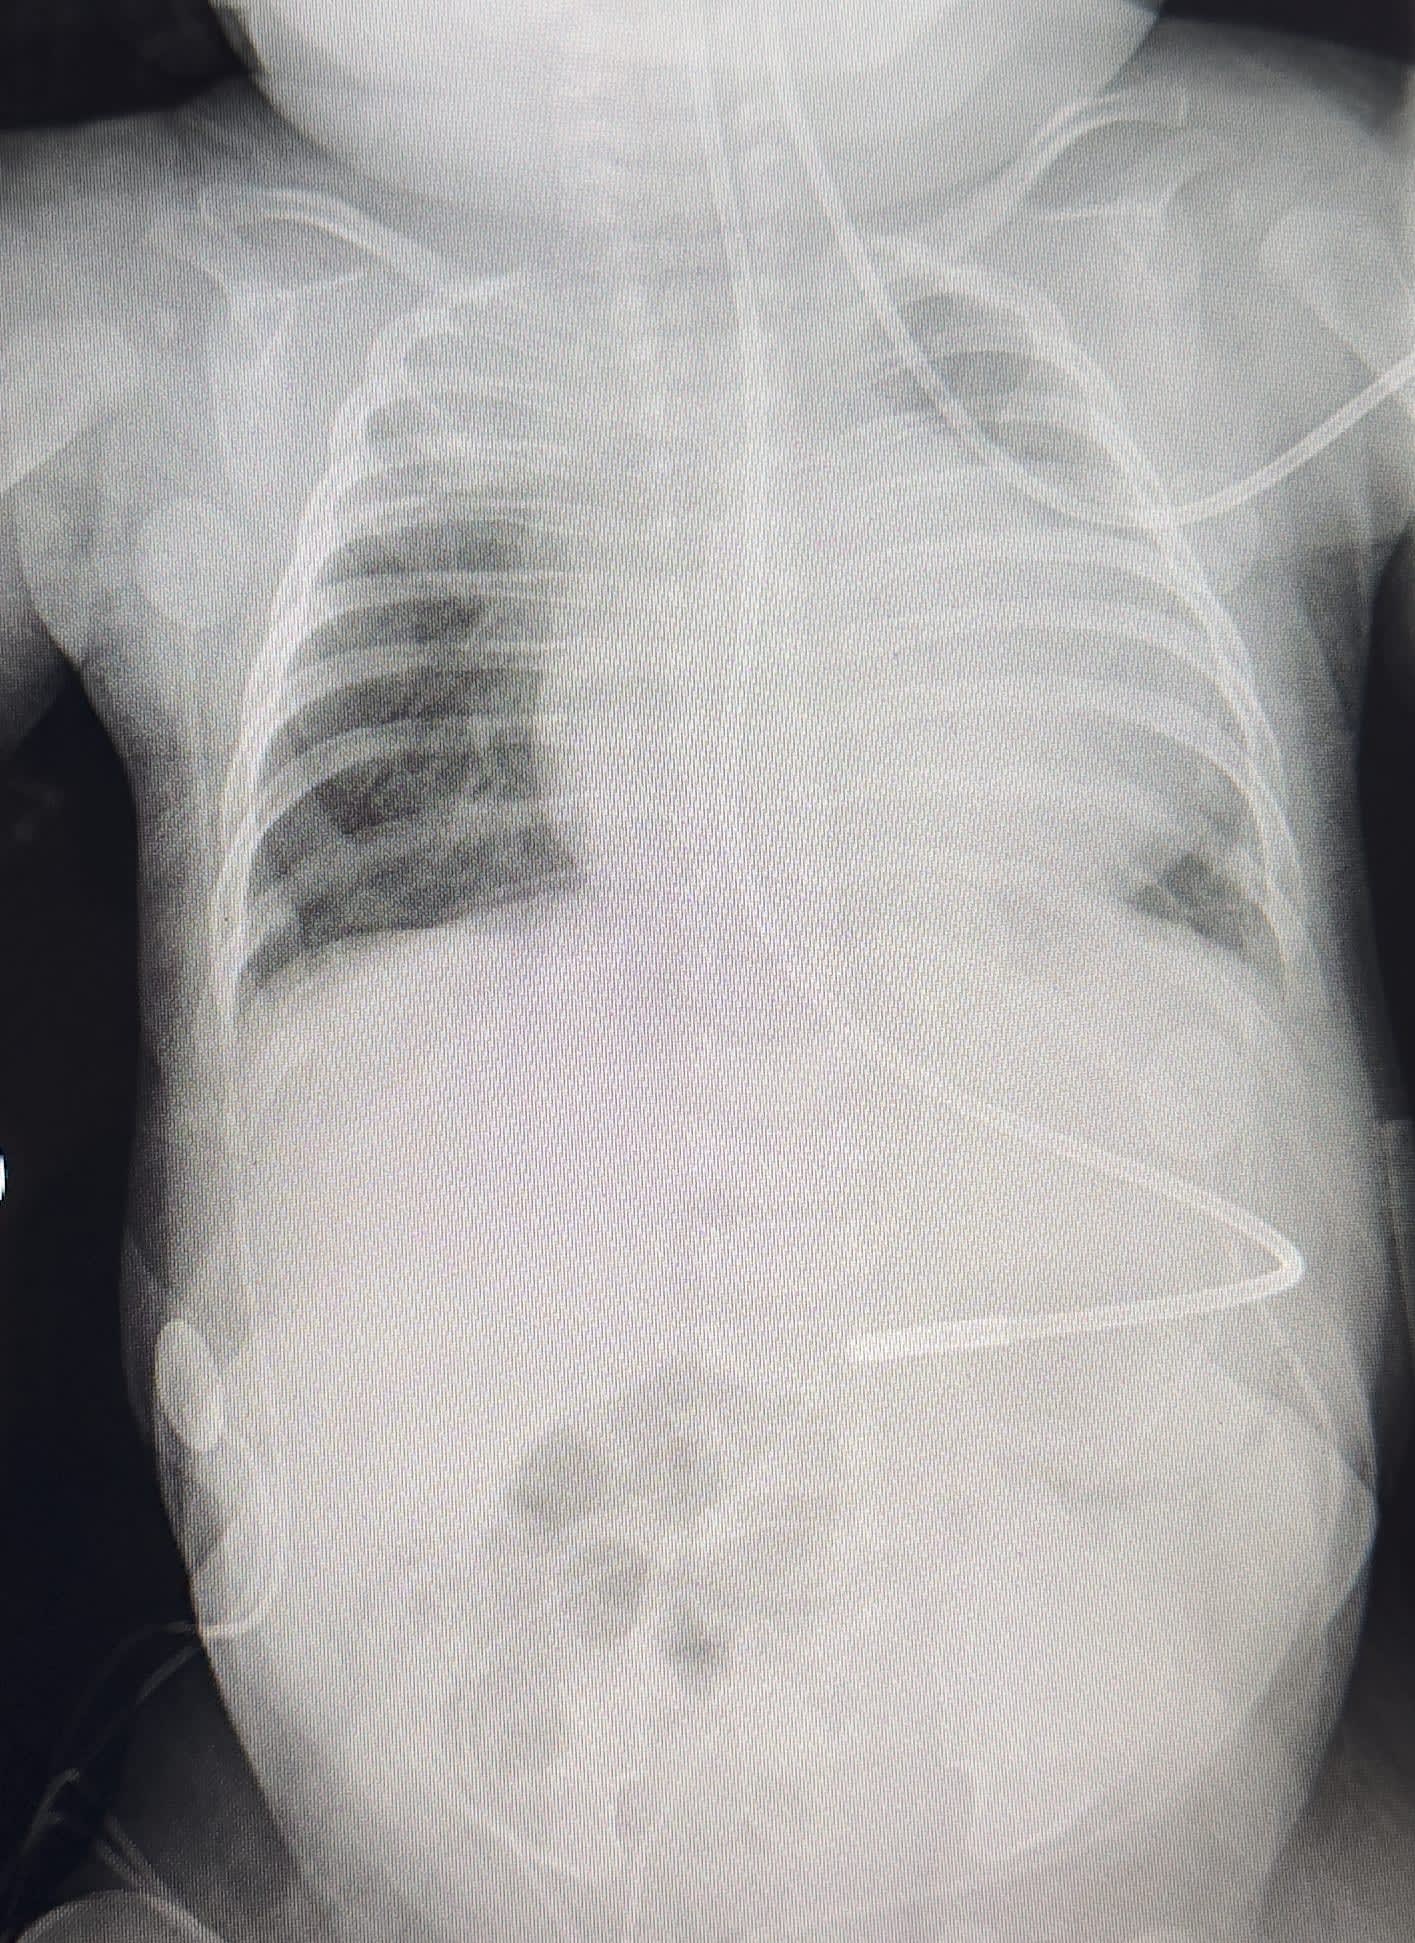

Good Morning sorry there hasn't been an update sooner, so there have been very little things over the past month, somedays there were no changes other days it would be small, it has been up and down we would move forward to be hit right back down somedays, so Illyana's RPA (Right Pulmonary Artery) is to big, tomorrow they will do open heart surgery on her again and reduce the size of her RPA, so what happens is when she coughs without positive pressure her right upper lobe collapses 100%, with positive pressure her right upper lobe collapses 60%-70% when she coughs, we will give an update when we know more about the surgery.

Illyana is doing better today, her lungs look better than they have ever looked, she is such a warrior she has made amazing strives to get healthier, they are continuing to drop her vent setting to wean her off of the vent, this morning they have paused her feeds in preparation to extubate today, we are so excited for how far she has come, we are thankful for all the prayers everyone has poured over us, we will update later on when she becomes extubated.

Update on Illyana, She is doing well but she is running a fever and her white blood cell is high so they sent her for a CT scan to check her chest, belly, lungs. She is still on the vent, we will know further plan of care soon.

Illyana has been paralyzed, they are needing her to stay still, she will not have her feeds for at least 5 days, Illyana has Portal venous gas in her intestines and the veins in her liver it was an accidental finding, she may have to have abdominal surgery won’t know nothing for a few days on this, they are giving her a blood transfusion as well. https://youtu.be/ReJU4ptmi0s Illyana is sedated pretty well due to her being getting agitated. They are starting a morphine drip to keep her comfortable from pain and help keep her calm while she is on the vent. Her CO2 levels are dropping but they want to keep her vented to see if they can get her little balloons that haven't been oope in her lungs to open. She getting the care has been needing. Please keep praying! God is healing her.

Illyana got intubated today about 2:30 this evening,her CO2 levels have improved since being on the vent. Please keep praying, pray for healing of her lungs and strength to get better and to find out what is causing this issue. Pray for the team of doctors and nurses caring for our baby girl.

Sorry we haven’t really given an update on Illyana, it has been a very exhausting through this journey to say the least, so her skin color looks better than it ever has, she is being weaned off different drip meds, she has came off the breathing tube and chest tubes and went to bipap and then down to cpap, she may go to vapatherm today but the top part of her right lung collapsed, once that is fixed she will be going on vapatherm, she still has a lot of milestones to hit but look at what God is doing.